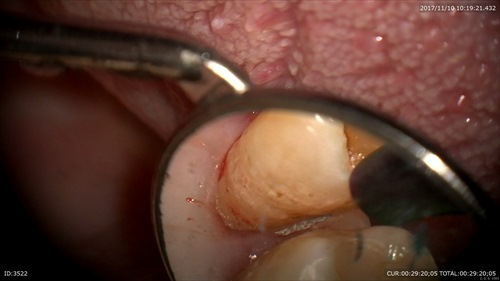

マイクロスコープだとこんなに見えます。歯茎の内部5mmを16倍で拡大、無痛クリーニングを行いました

実はこの方は他院で定期的に(先日まで)歯石とりをされていた方です。これを見ていかがでしょうか?本人はこの画像をみてショックを受けていました。

「定期的に通い痛い思いをして歯石を取っていた」とのことです。

ここはルーペや裸眼では見えませんしこの部分(ポケット4mm以上)の歯石は歯周病の専門医でないと歯石やバイオフィルムをかなりの確率で取り残すと論文でも実証されています。下記参照

「3mmまでの浅い歯周ポケットでも処置後に14%歯石の取り残しがあり、4~6mmでは24%、6mm以上では50%取り残しているというエビデンス(医学的根拠)が発表されています。

(エビデンス論文:Caffesse RG et al: Scaling and root planing with and without periodontal flap surgery. J Clin Periodontol, 13: 205-210, 1986.)」

だから当院では歯周病治療やメンテナンスであっても衛生士ではなくこの領域は私が無痛で行います。

昔は歯茎を切って治療していました。今はマイクロスコープで切らないでしかも無痛で治します。内視鏡のような方法です。